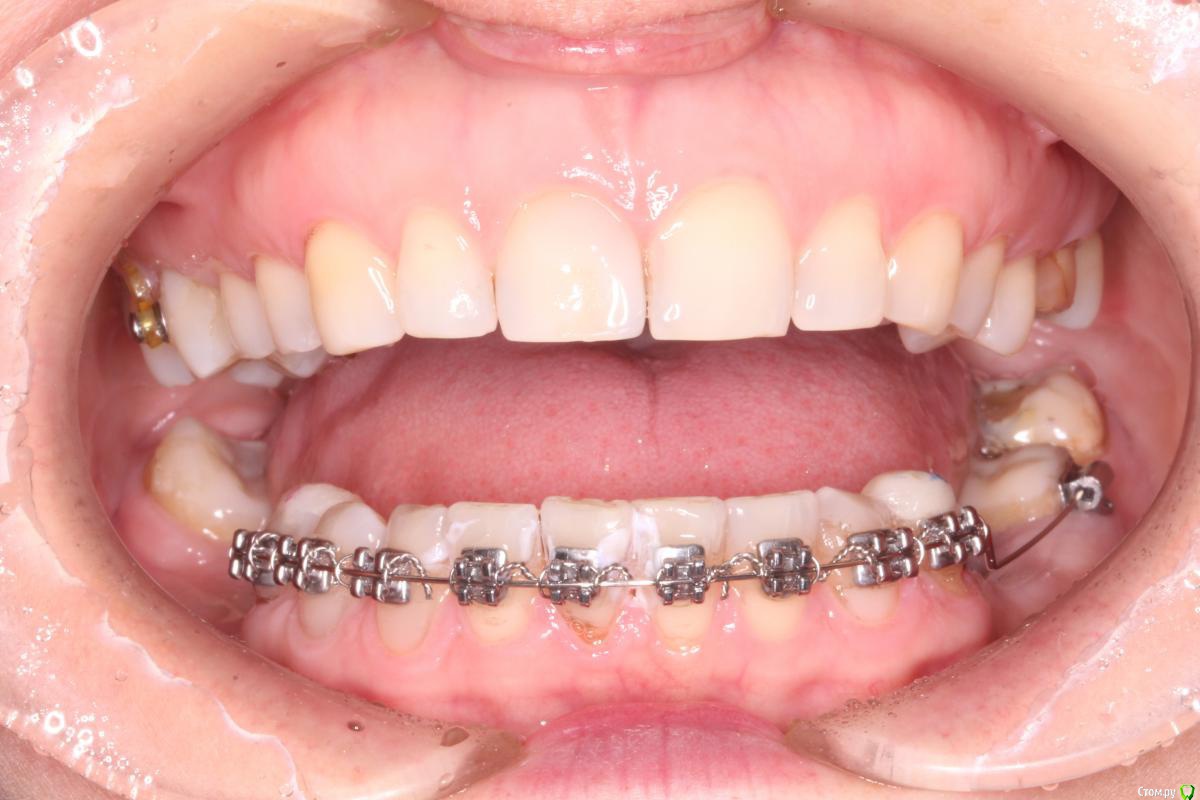

Yana guapa Опубликовано 3 сентября, 2015 Поделиться Опубликовано 3 сентября, 2015 судя по фасеткам стираемости лигирование и переклейка здесь не помогут. Нижний зубной ряд нуждается в расширении. Но это невозможно при таком оверджет. Ну только если жесткий стрипинг. 1 Ссылка на комментарий

Yana guapa Опубликовано 3 сентября, 2015 Поделиться Опубликовано 3 сентября, 2015 думаю если убрать ок.накладки и проверить контакты - вся передняя поверхность нижних резцов окрасится. такие контакты плотные не дают стать ровно зубам. Надо расширять верх (ну или хотя бы изменить инклинацию верхних резцов) 2 Ссылка на комментарий

Monkey Опубликовано 3 сентября, 2015 Автор Поделиться Опубликовано 3 сентября, 2015 (изменено) судя по фасеткам стираемости лигирование и переклейка здесь не помогут. Нижний зубной ряд нуждается в расширении. Но это невозможно при таком оверджет. Ну только если жесткий стрипинг. Да, по перекрытию я смотрела, пространство (небольшое) есть. Я думаю, я еще сама связками (8-ками) заузила.Сейчас все зубы залигировала по одному и, действительно, попробую прямоугольную дугу- торк пойдет (брекеты на резцах 0*) может быть за счет этого расправятся...ну и плюс посепарирую еще.Спасибо за советы! Изменено 3 сентября, 2015 пользователем Monkey Ссылка на комментарий

Yana guapa Опубликовано 3 сентября, 2015 Поделиться Опубликовано 3 сентября, 2015 Да, по перекрытию я смотрела, пространство (небольшое) есть. Я думаю, я еще сама связками (8-ками) заузила. Про ВЧ речь идет?Были брекеты вверху? Сейчас все зубы залигировала по одному и, действительно, попробую прямоугольную дугу- торк пойдет (брекеты на резцах 0*) может быть за счет этого расправятся.... не думаю, что это поможет. при отсутвие должного оверджета не получится протрузии, а значит и разворачиваться некуда будет. и прямоугольная дуга не поможет при таком дефиците места. процесс пойдет только тогда, когда появится место. это либо 1. создание оверджета (за счет ВЧ), или 2. сепарация НЧ 3. как вариант дистализация премоляров (если окклюзионные контакты позволяют (как сейчас по прикусу в боковых отделах? есть фото?) ) Ссылка на комментарий

Monkey Опубликовано 6 сентября, 2015 Автор Поделиться Опубликовано 6 сентября, 2015 Про ВЧ речь идет?Были брекеты вверху? не думаю, что это поможет. при отсутвие должного оверджета не получится протрузии, а значит и разворачиваться некуда будет. и прямоугольная дуга не поможет при таком дефиците места. процесс пойдет только тогда, когда появится место. это либо 1. создание оверджета (за счет ВЧ), или 2. сепарация НЧ 3. как вариант дистализация премоляров (если окклюзионные контакты позволяют (как сейчас по прикусу в боковых отделах? есть фото?) ) Нет, брекетов на вч не было. Фотографии боковых отделов есть только июньские. Дистализировать там больше нельзя.Выходит вариант один - сепарировать весь фронт? Ссылка на комментарий